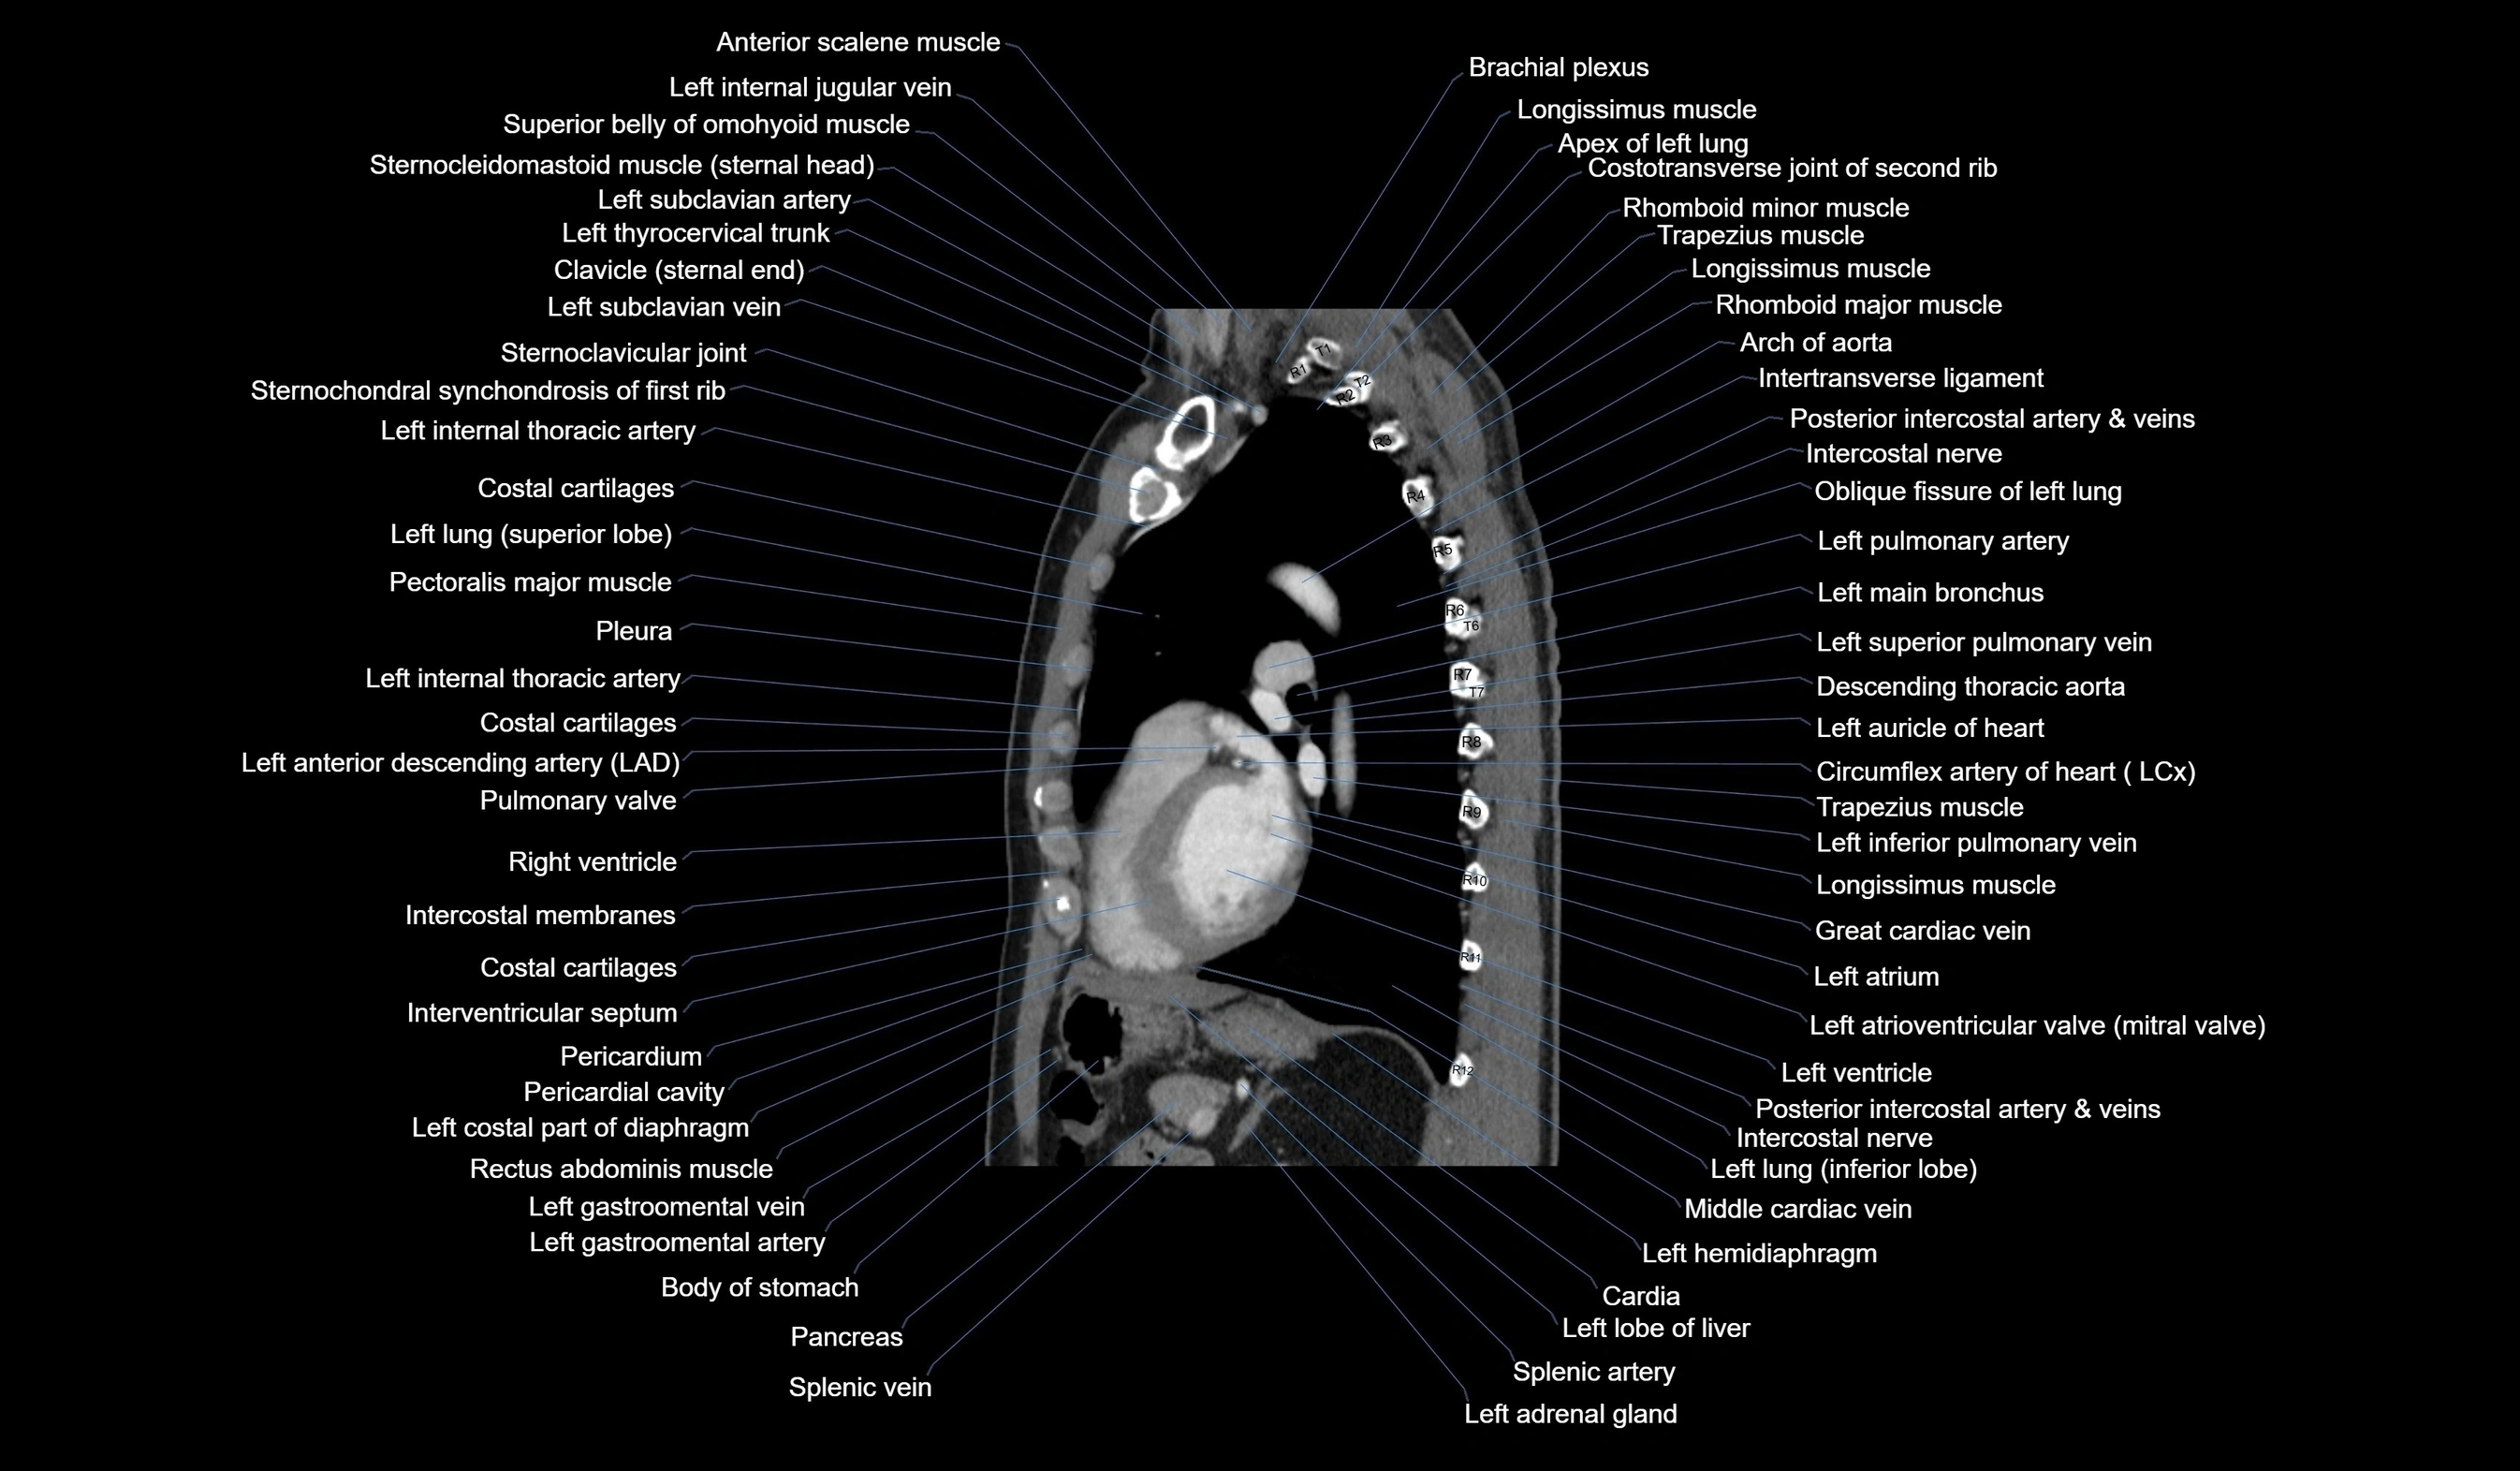

CT images